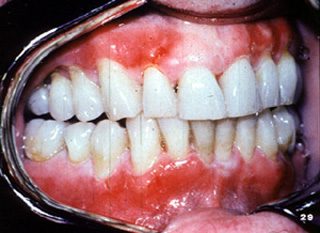

El penfigoide benigno tiene una marcada tendencia a involucrar la encía marginal. La descripción clínica a menudo usada para estas lesiones es "gingivitis descamativa" Debe señalarse que ésta es sólo una descripción clínica y no un diagnóstico definitivo. En la encía  tiene una marcada apariencia eritematosa.

Aquí hay otro paciente con la encía afectada por la enfermedada..